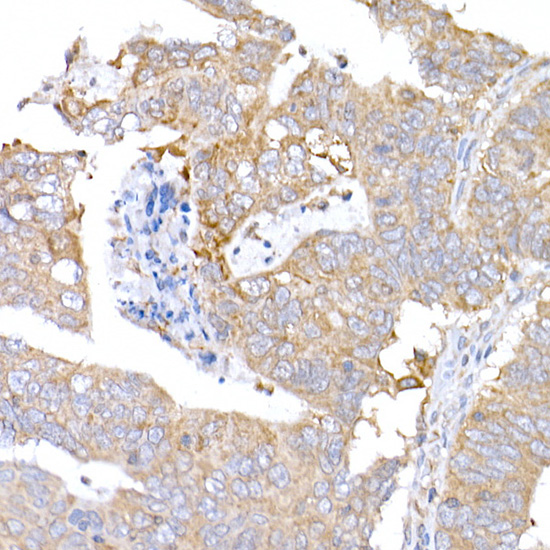

Immunohistochemistry of paraffin-embedded liver cancer using MAGED1 antibody at dilution of 1:100.